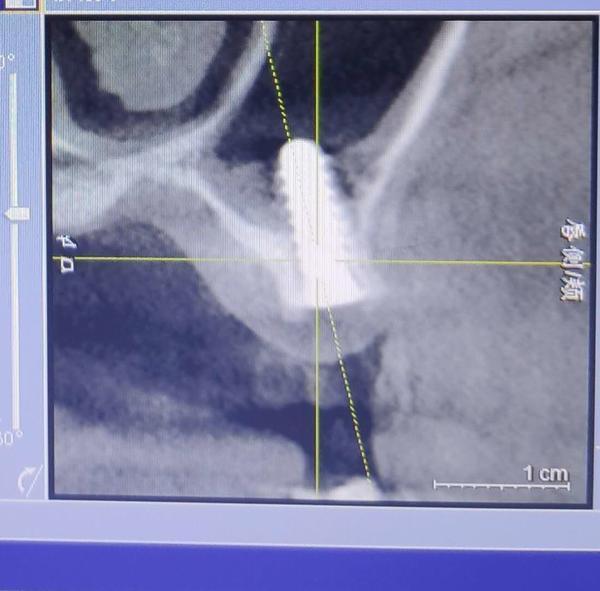

2019年下半年,在出現(xiàn)了不適反應(yīng)后,葉女士到沈陽(yáng)一家部隊(duì)醫(yī)院口腔門診求醫(yī)。經(jīng)CT等檢查,她才發(fā)現(xiàn),原來有一顆種植體已經(jīng)進(jìn)入了她的上頜竇腔。

葉女士做出的影像檢查結(jié)果顯示,其中一顆植體已經(jīng)進(jìn)入上頜竇腔內(nèi)。

2019年7月,在出具的診斷證明上,沈陽(yáng)市當(dāng)?shù)匾患胰揍t(yī)院的知名口腔診療專家說,該種植體已經(jīng)進(jìn)入上頜竇腔,需要取出。